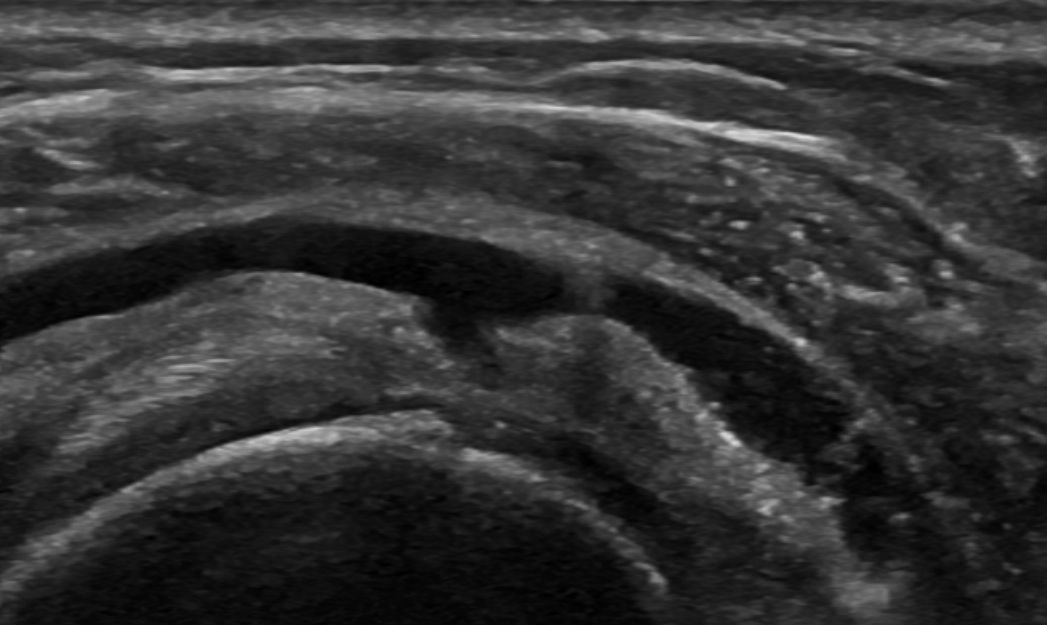

Supraspinatus bursal surface partial tear seen on bursography